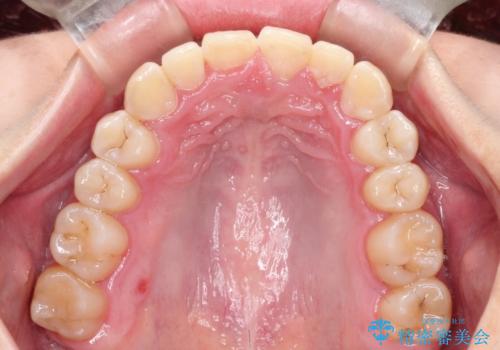

ハーフリンガル ワイヤー矯正による非抜歯・過蓋咬合の治療

- 非抜歯、大臼歯遠心移動による臼歯関係の是正・過蓋の改善をハーフリンガル・ワイヤー矯正にて計画した。

現在過蓋咬合の非抜歯治療はマウスピースで行うのが第1選択といっても過言ではありません。